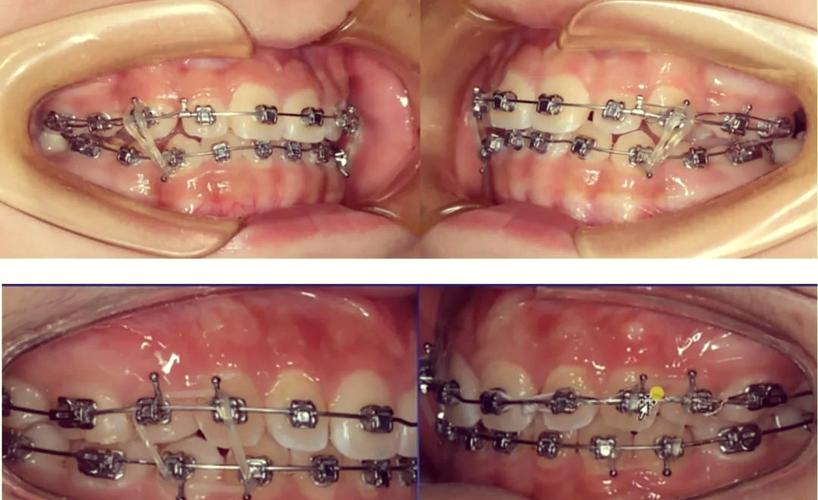

正畸牵引圈是正畸治疗中常用的辅助装置,主要用于牵引牙齿、关闭间隙、纠正牙齿位置异常等,其弯制质量直接影响治疗效果和患者舒适度,弯制正畸牵引圈需要结合牙齿解剖形态、移动方向及生物力学原理,通过精细操作实现精准形态,以下从工具准备、弯制步骤、技巧要点、常见问题及解决方法等方面详细说明正畸牵引圈的弯制方法。

牵引钩是牵引力的直接作用点,需根据牵引方向调整角度和长度:

- 垂直牵引钩(用于牵引牙齿向垂直方向移动):在标记的牵引钩位置,用细丝钳钳尖夹住钢丝,向远离主体的方向弯制“L”形,垂直臂长度5-7mm(末端向舌侧或唇侧回折1-2mm,避免刺伤软组织)。

- 水平牵引钩(用于近远中牵引):弯制“7”形,水平臂沿牙弓方向,长度与牙间隙一致(约3-5mm),末端同样回折。

- 抗扭转牵引钩:在主体上增加附加牵引臂,用结扎丝钳弯制“U”形小钩,与主体呈45°角,增强抗扭转能力。

- 调整弧度贴合度:将弯制好的牵引圈放在模型或石膏牙上,检查是否与牙冠表面贴合,避免压迫牙龈乳头;若不贴合,用细丝钳轻柔调整主体弧度,直至牵引圈能稳定套入牙冠且无翘动。

- 修整牵引钩方向:用梯形钳调整牵引钩角度,确保牵引力方向与牙齿移动方向一致(如牵引尖牙远中移动,牵引钩应指向远中偏龈方)。